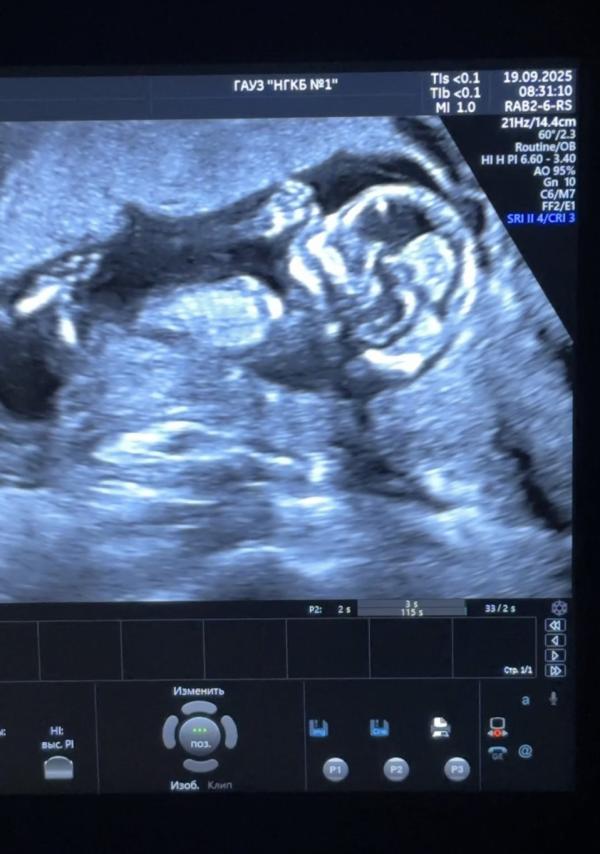

Сходили на скрининг) Мужа пригласили и нам вместе всё рассказали, показали. Муж записал видео🥰по узи всё хорошо. Смешнявый такой бекарас😅